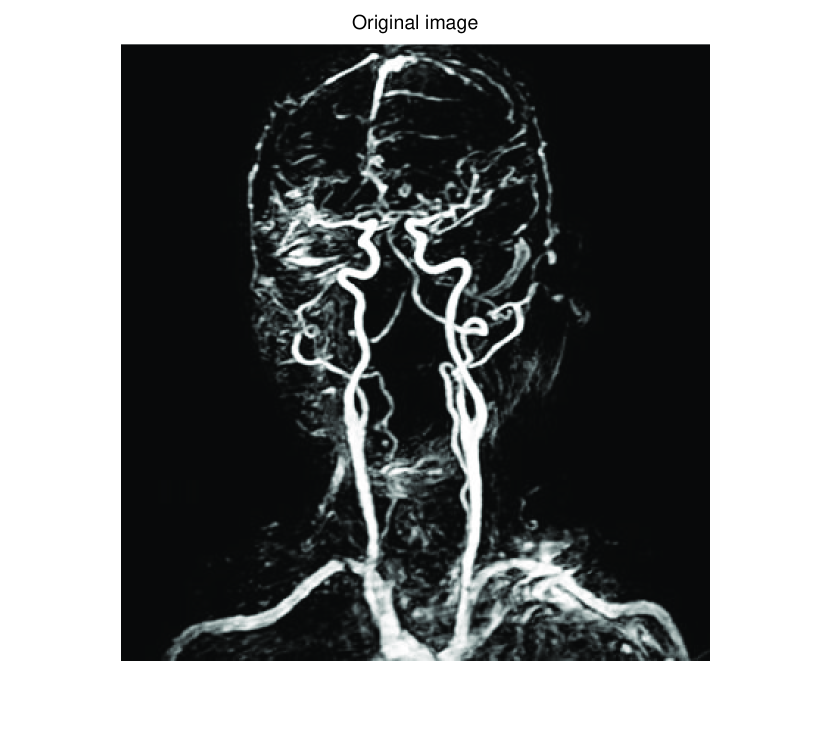

In this subsection, we demonstrate performances of ISVTA on image inpainting problems. The ISVTA is tested on some medical grace images (255×192255192255\times 192 Brain angiography image (BAI), 395×549395549395\times 549 Hand angiography image (HAI) and 419×400419400419\times 400 Intracranial venous image (IVI)). We use the SVD to obtain their approximated low-rank images with rank r=30,40,30𝑟304030r=30,40,30, respectively. Numerical results of ISVTA for theses low-rank image inpainting problems are reported in Table 5, 6, 7, 8.

Refer to caption

Figure 3: Original 255×192255192255\times 192 BAI and its approximation with rank 30.

Figure 6: Comparisons of ISVTA, SVTA and SVPA for recovering the approximated low-rank BAI with SR=0.40.